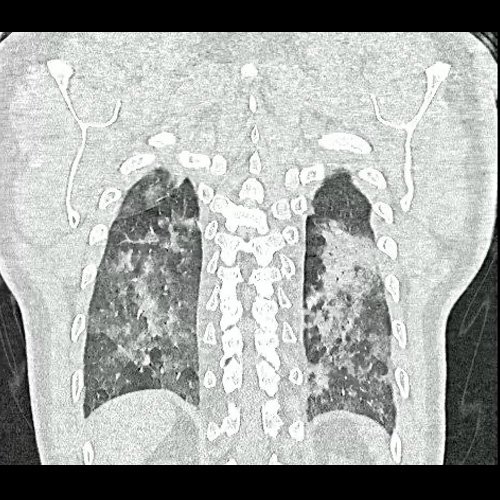

- Tomografía de tórax sin contraste endovenoso (Dia 0):Se observan múltiples áreas de consolidación parenquimatosa con broncograma aéreo y de distribución difusa por ambos pulmones, predominando en los lóbulos inferiores, asociadas a engrosamiento de los septos y rodeadas de tenue vidrio esmerilado. Se identifican estructuras ganglionares lateroaórticas, pretraqueales y subcarinales, ninguna de ellas sin alcanzar rango megálico.

Tomografia de torax sin contraste endovenosos (Ventana pulmonar- Corte coronal)

Tomografia de torax sin contraste endovenosos (Ventana pulmonar- Corte coronal)

Tomografia de torax sin contraste endovenosos (Ventana pulmonar- Corte coronal)

Tomografia de torax sin contraste endovenosos (Ventana pulmonar- Corte coronal)